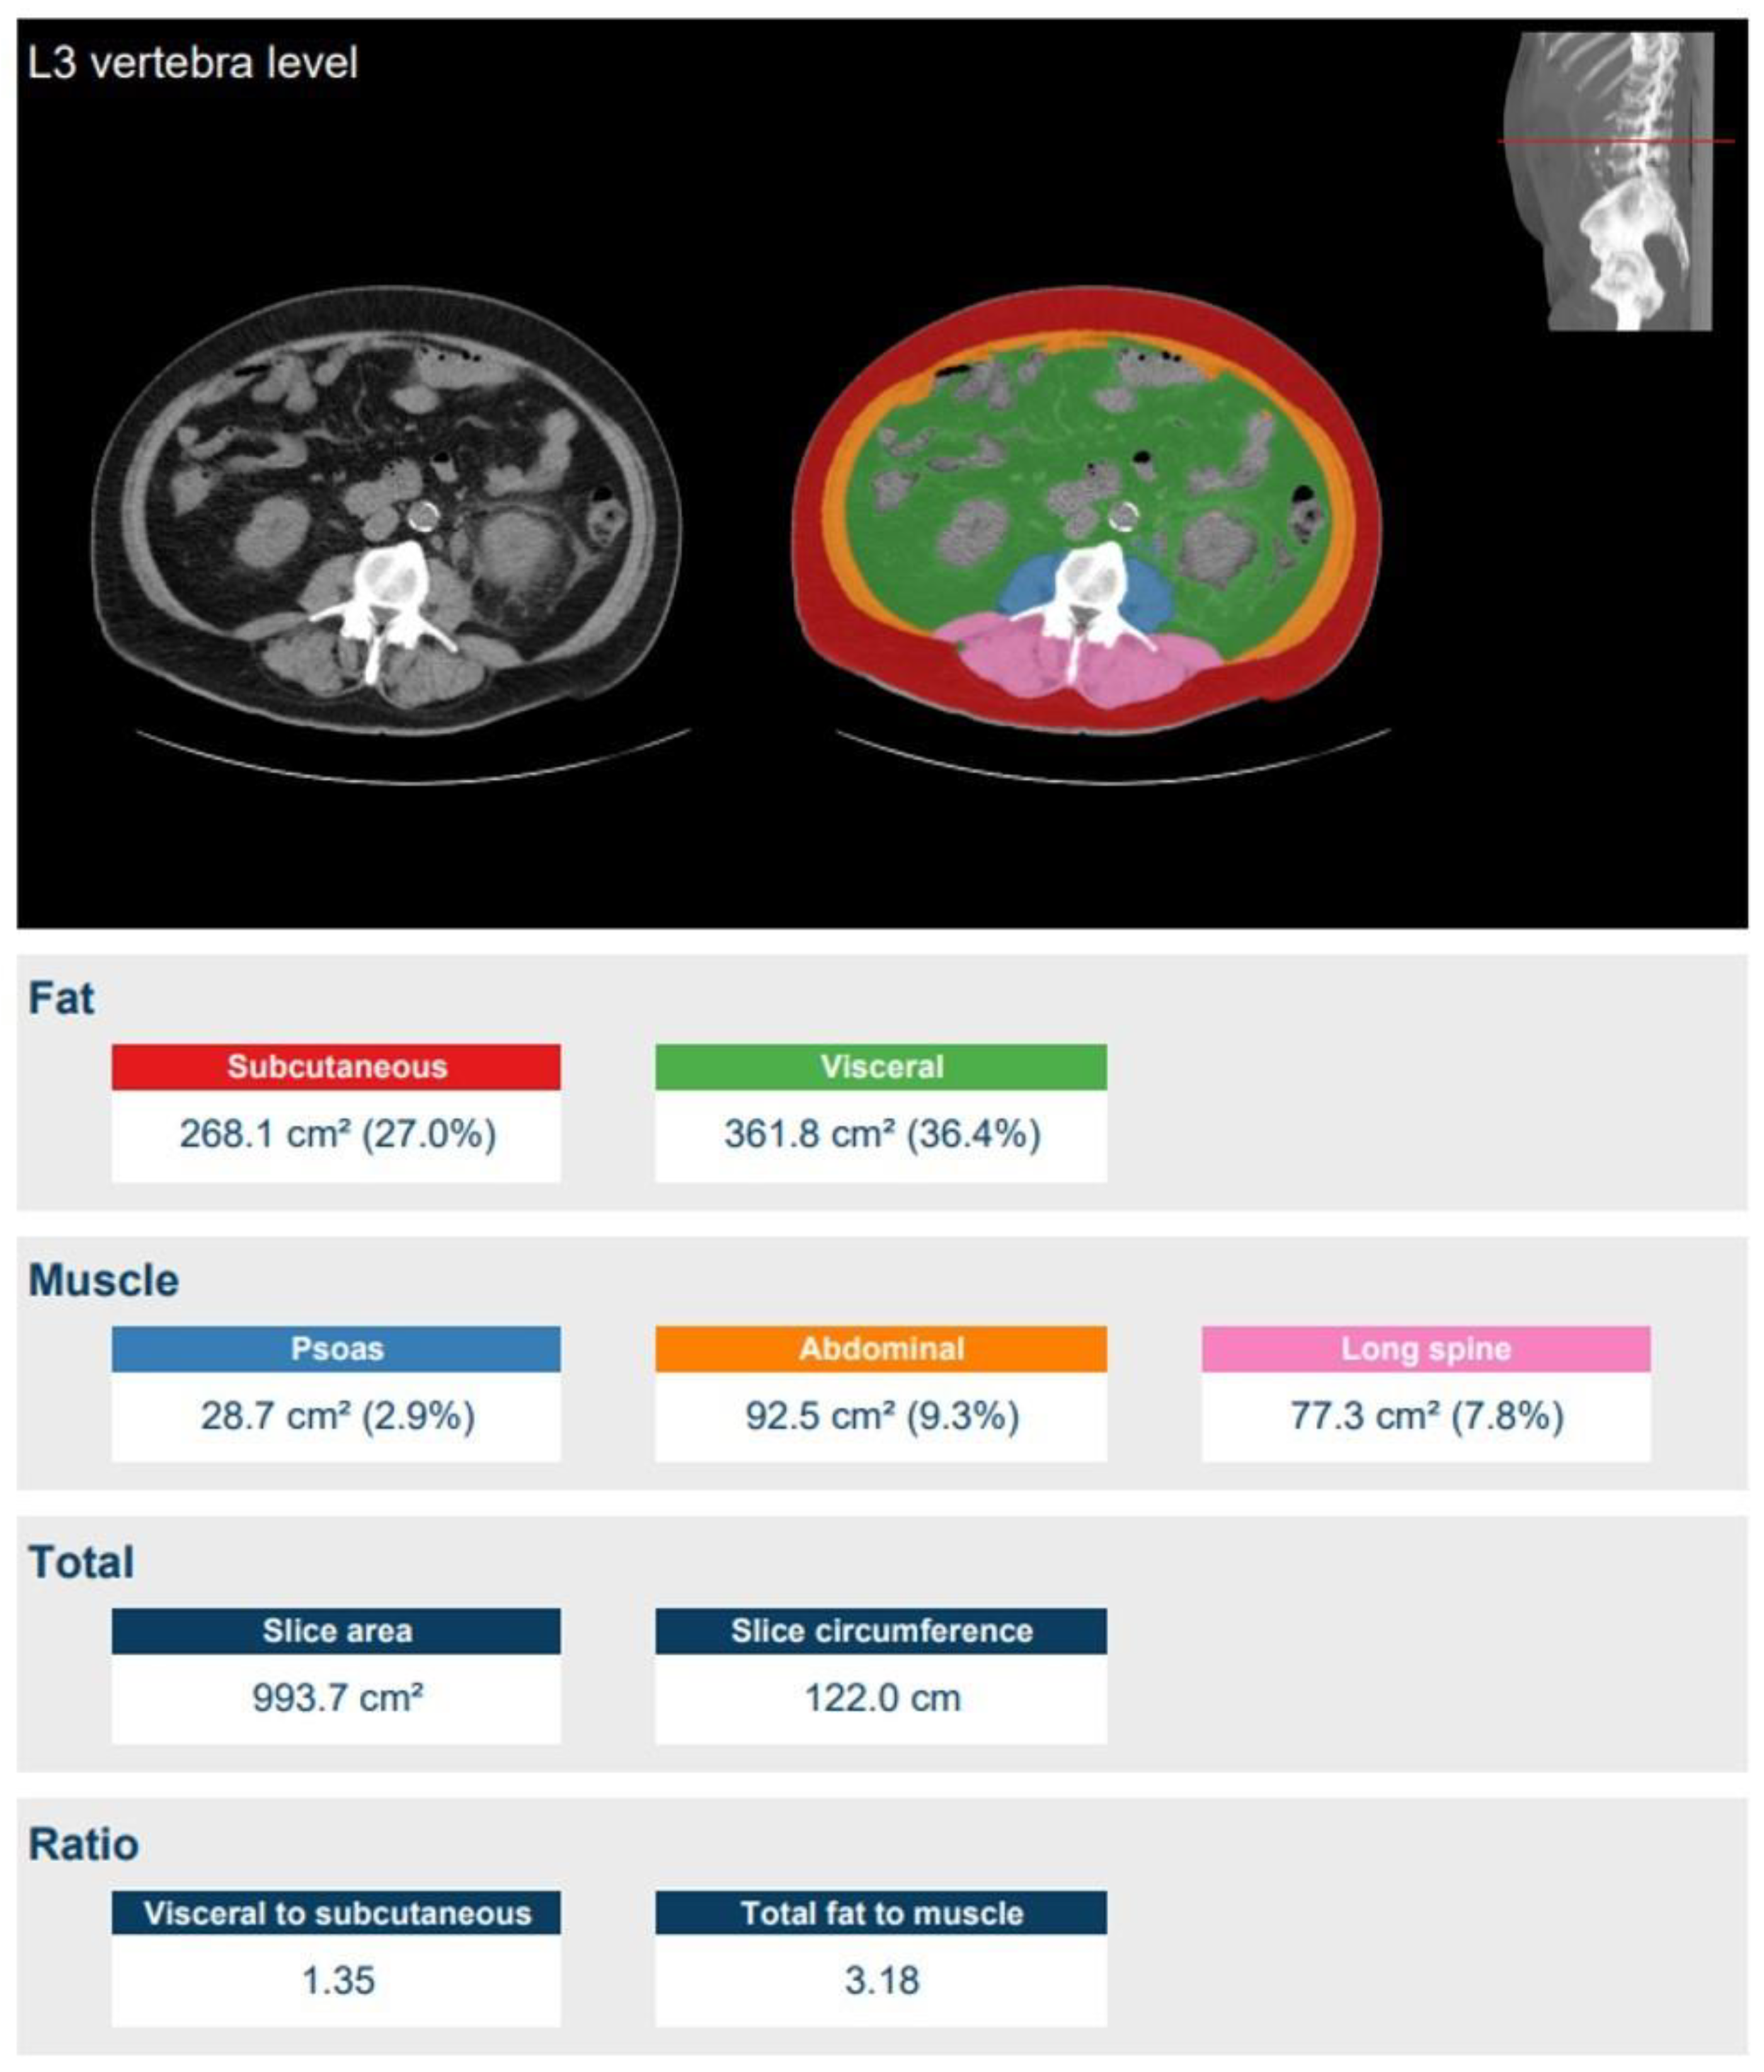

- Moeskops, P.; de Vos, B.; Veldhuis, W.B.; de Jong, P.A.; Išgum, I.; Leiner, T. Automatic quantification of body composition at L3 vertebra level with convolutional neural networks. Eur. Congr. Radiol. 2020. [Google Scholar] [CrossRef]